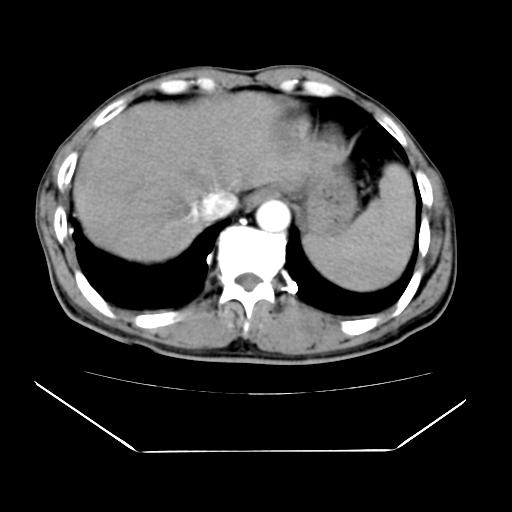

男性,55岁,外院体检afp明显升高,但b超未发现异常,否认乙肝病史。来我院ct增强。有延时扫描。

延时扫描完全充填,血管瘤

肝脏右叶动脉期可见低密度影,至延迟期被充填,考虑血管瘤可能性大。

肝右叶病灶

不排除肝右叶肝癌可能。

如果这个是癌灶的话则下腔静脉有瘤栓可能

肝6段血管瘤

血管瘤可能性大。

考虑肝右静脉影。